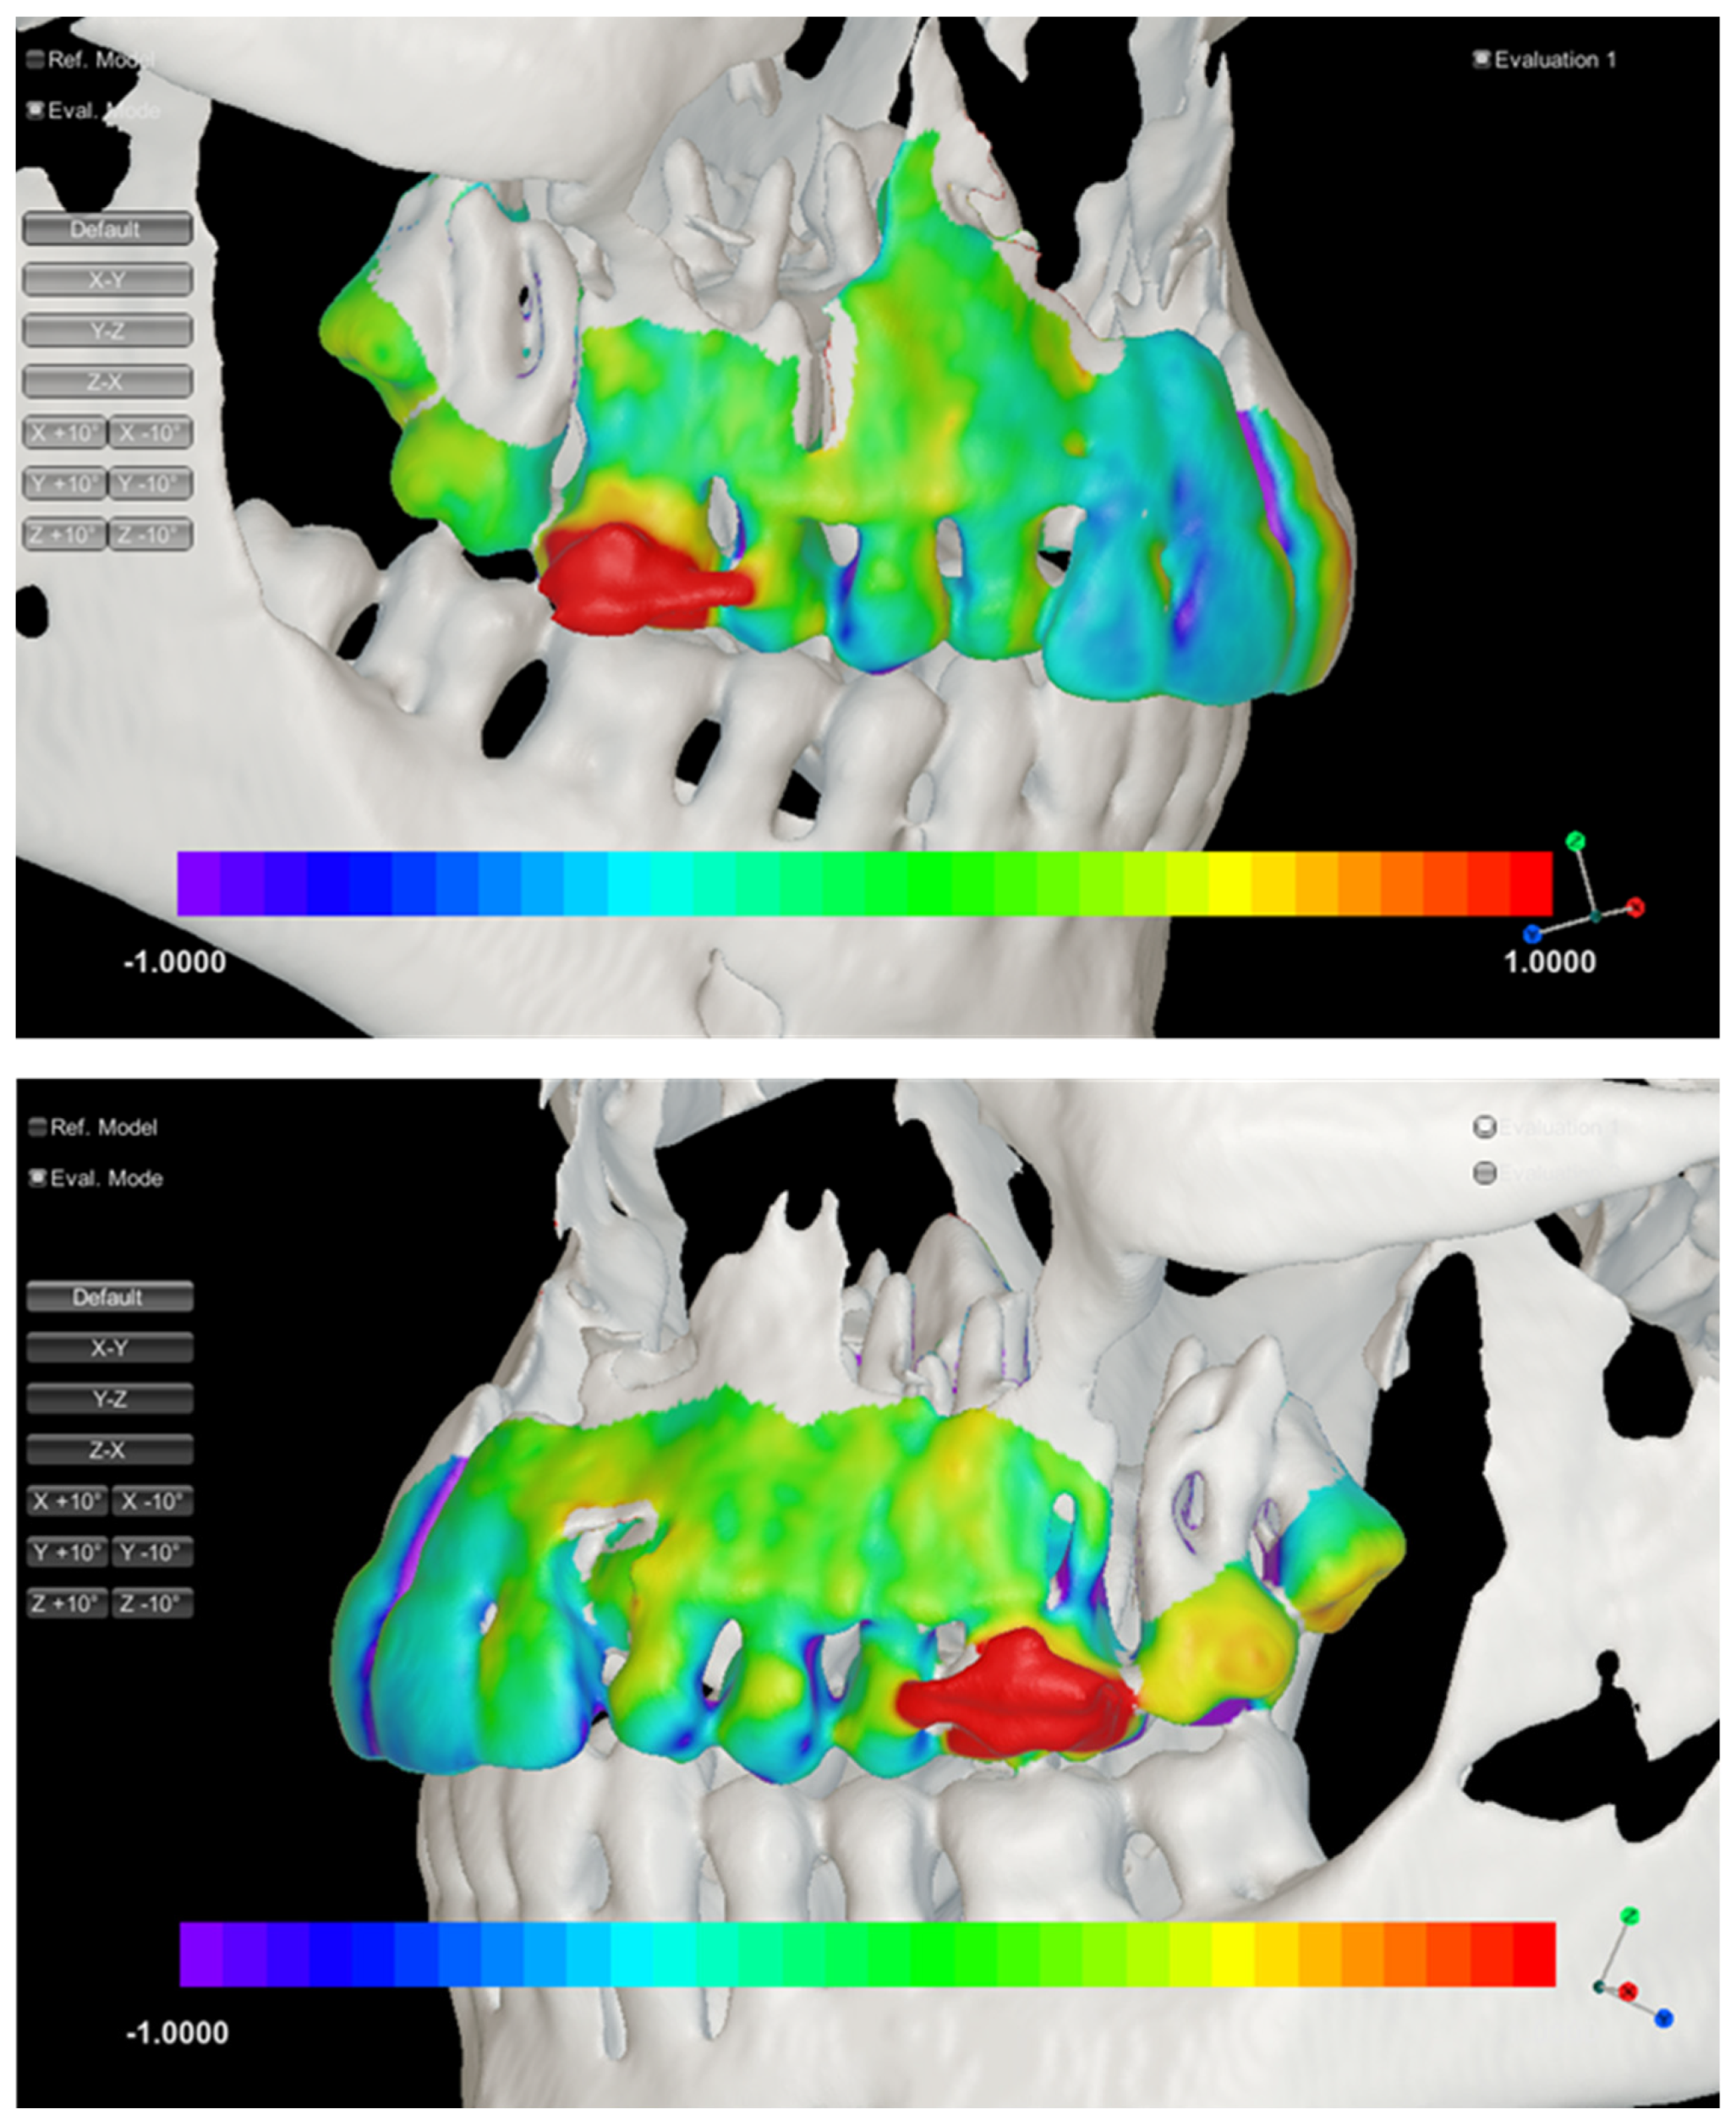

2.4. Three-Dimensional Visualization

3. Results